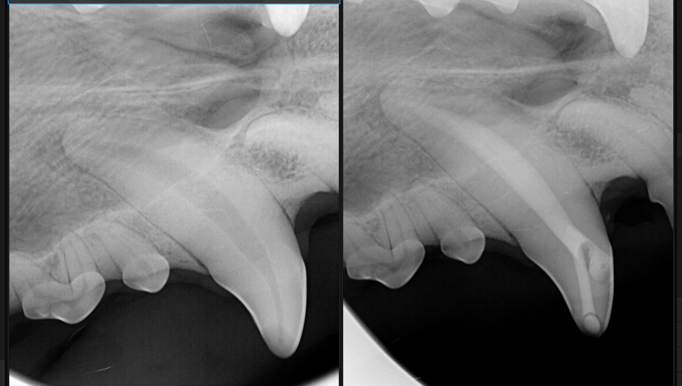

Tooth fractures are common in dogs and cats, particularly in younger animals. Left untreated, they can become infected and very painful. In this case study, we will hear about Stuart and Cleo, and how their fractures were treated so that the broken teeth could be preserved.

Dental Salvage: A Tale of Two Teeth